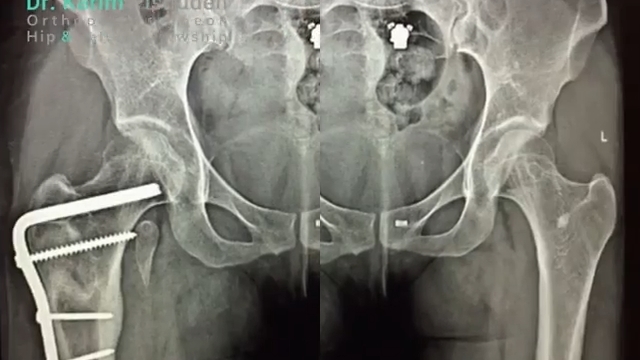

شکستگی ساب تروکانتریک